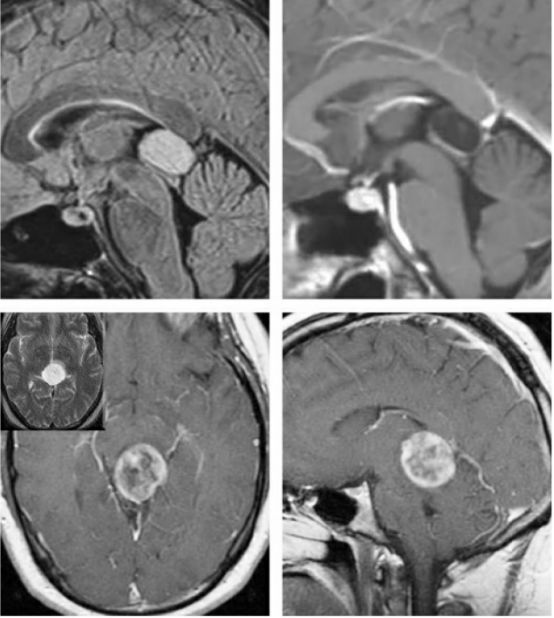

图2. 各种类型的松果体区病变。上排所示为一例松果体囊肿,注意其只有薄层环形强化;下排所示为一例顶盖区毛细胞型星形细胞瘤;而其他病变,如生殖细胞瘤、松果体母细胞瘤和胶质瘤卒中请阅读Selection of Operative Corridor章节。